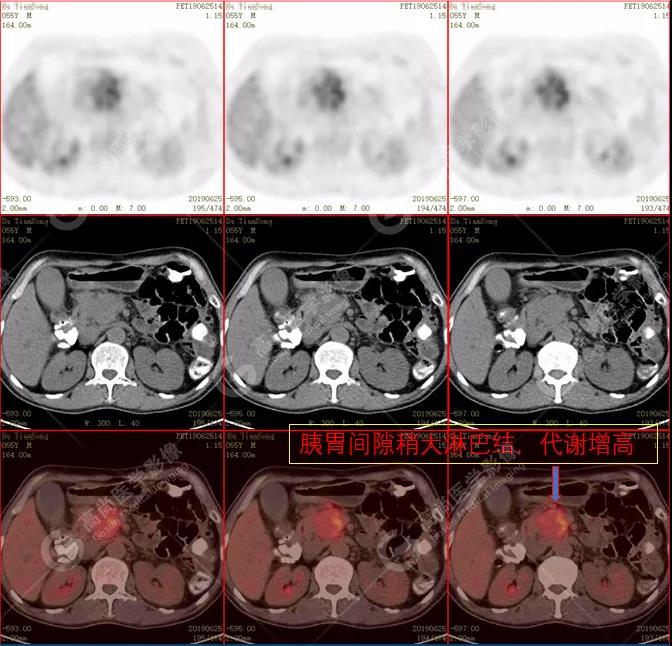

(2)胰周(胰胃間隙)稍大淋巴結(jié),代謝增高。